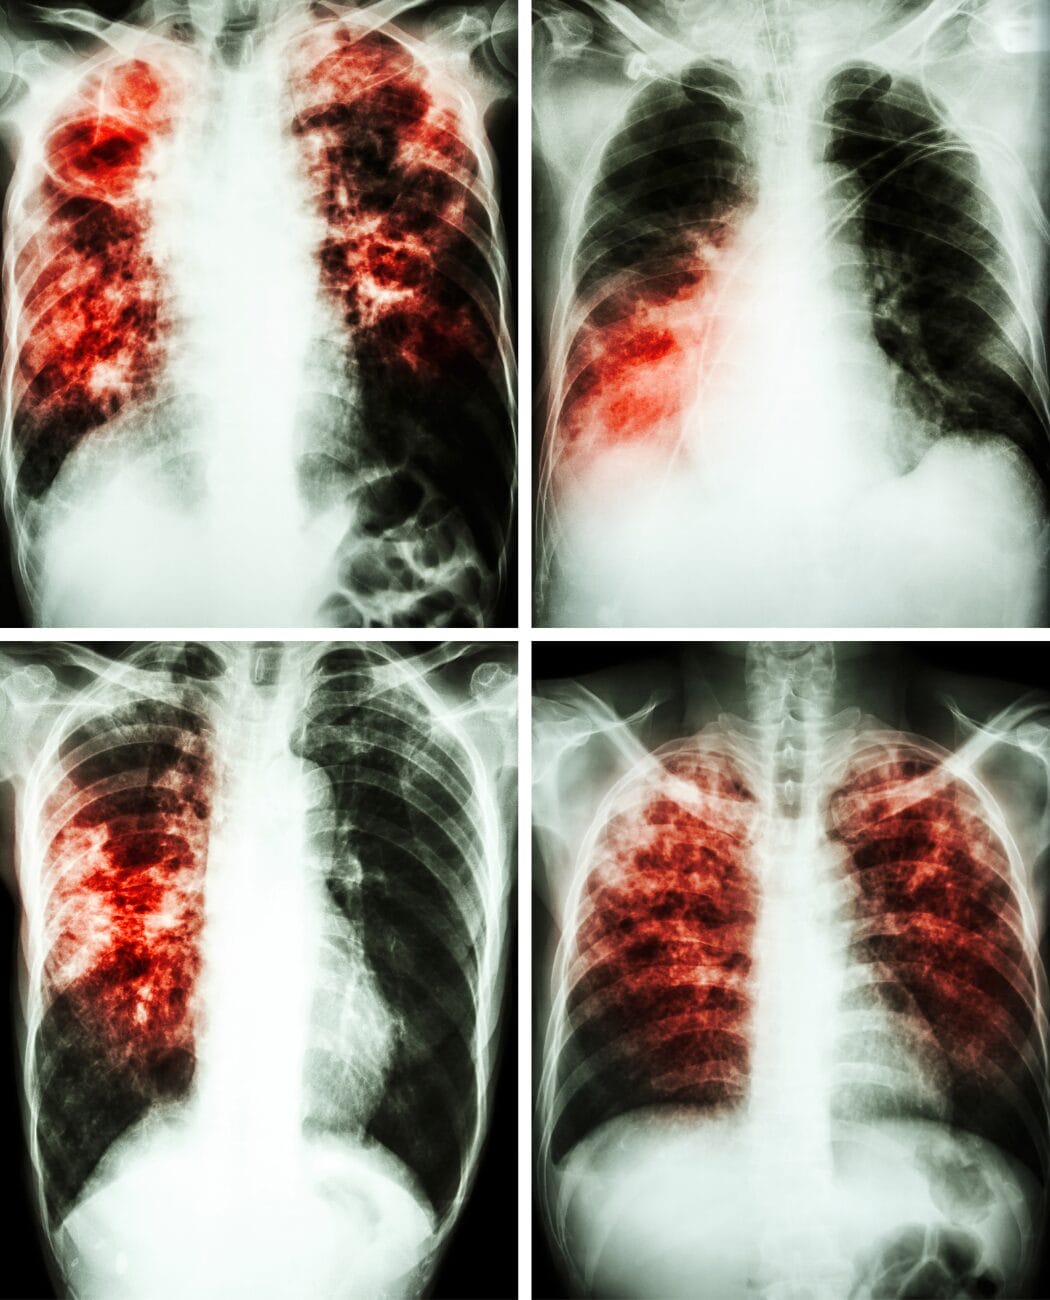

Diagnosing lung and breathing disorders involves a comprehensive assessment of an individual's respiratory health to identify any abnormalities or impairments. This process often includes a combination of:

- medical history reviews

- physical examinations

- specialized tests

- pulmonary function tests

- imaging studies.

Once a precise diagnosis is established, healthcare professionals can formulate tailored treatment plans to address the specific disorder or condition. There are a number disorders or conditions that RRTs handle on a daily basis. They can include:

- Sleep Apnea

- Emphysema

- Bronchitis

- Chronic Obstructive Pulmonary Disease (COPD)

- Asthma

- Cystic Fibrosis

- Muscular Dystrophy

- Parkinson's Disease

- Amyotrophic Lateral Sclerosis (ALS)

- COVID-19

- Many more...

Treatment methods may vary depending on the nature and severity of the respiratory issue, ranging from lifestyle modifications and medication regimens to more advanced interventions such as respiratory therapies or surgical procedures. The ultimate goal is to optimize lung function, alleviate symptoms, and enhance overall respiratory well-being, ensuring that individuals receive personalized and effective care based on their unique medical needs.